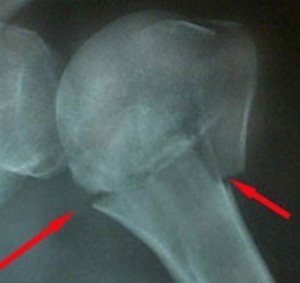

Диагноз уточняется с помощью рентгенографии сустава плеча. Она делается в двух проекциях: аксиальной и прямой. Аксиальный снимок делают, отводя плечо под углом 30-40 градусов от туловища. На больший угол отводить плечо не рекомендуется, так как смещение отломков может быть сильнее. Если повреждение вызывает сомнения, делают КТ сустава.

Сложно диагностировать вколоченные травмы хирургической шейки, потому что у них нет явных клинических признаков.